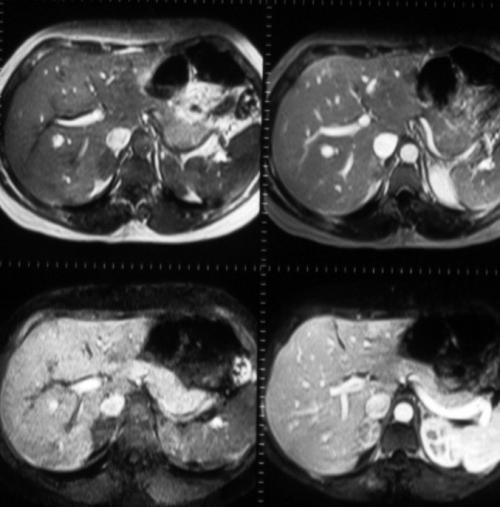

Until recently, conventional magnetic resonance (MR) imaging of the pancreas was limited by motion artifacts (respiratory, vascular, and bowel peristaltic) and poor spatial resolution. Recent technique innovations in MR imaging hardware and software (fast imaging) have allowed these problems to be overcome with acquisition images similar to those obtained with spiral computed tomography (CT) (Figure 1).

Figure 1. MR study of the pancreas: normal anatomy. T1 RF fast breath-hold images before and after intravenous administration of gadolinium-DTPA (up) T1 RF fast fat suppressed breath-hold images before and after intravenous administration of gadolinium-DTPA (down) show normal enhancement of the pancreatic parenchyma.

MR standard examinations of the pancreas require fat suppressed breath-hold T1- and non-breath-hold T2-weighted images; contrast agent is used especially in the fast imaging studies with acquisition of dynamic study.